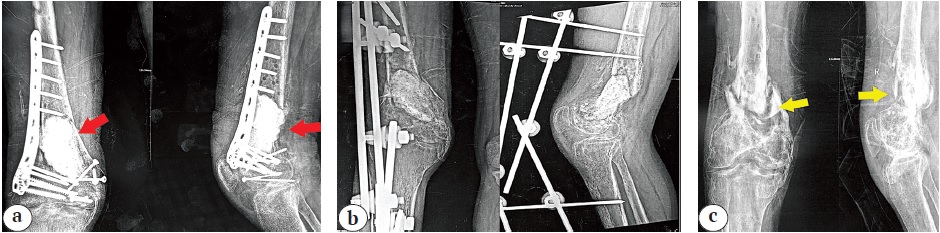

The described surgical technique is illustrated by the clinical case of a 32-year-old male patient who presented to us with an infected nonunited distal femoral fracture that was managed by a two-stage approach (Figures 1, 2, 3).

Figure 1. Admission X-rays of a 32-year-old male patient, who gave a history of a previous open distal femur fracture, which was treated initially with open reduction and internal fixation and got infected. Over two years, he had five surgeries (all included a sort of debridement):

a — initial fixation and application of a cement spacer (red arrowheads), which failed;

b — hardware was removed, and external fixation was applied;

c — lastly, after reinfection, all hardware was removed, and the patient presented with an infected nonunited distal femoral fracture (yellow arrowheads) with an open sinus on the lateral aspect of the distal thigh